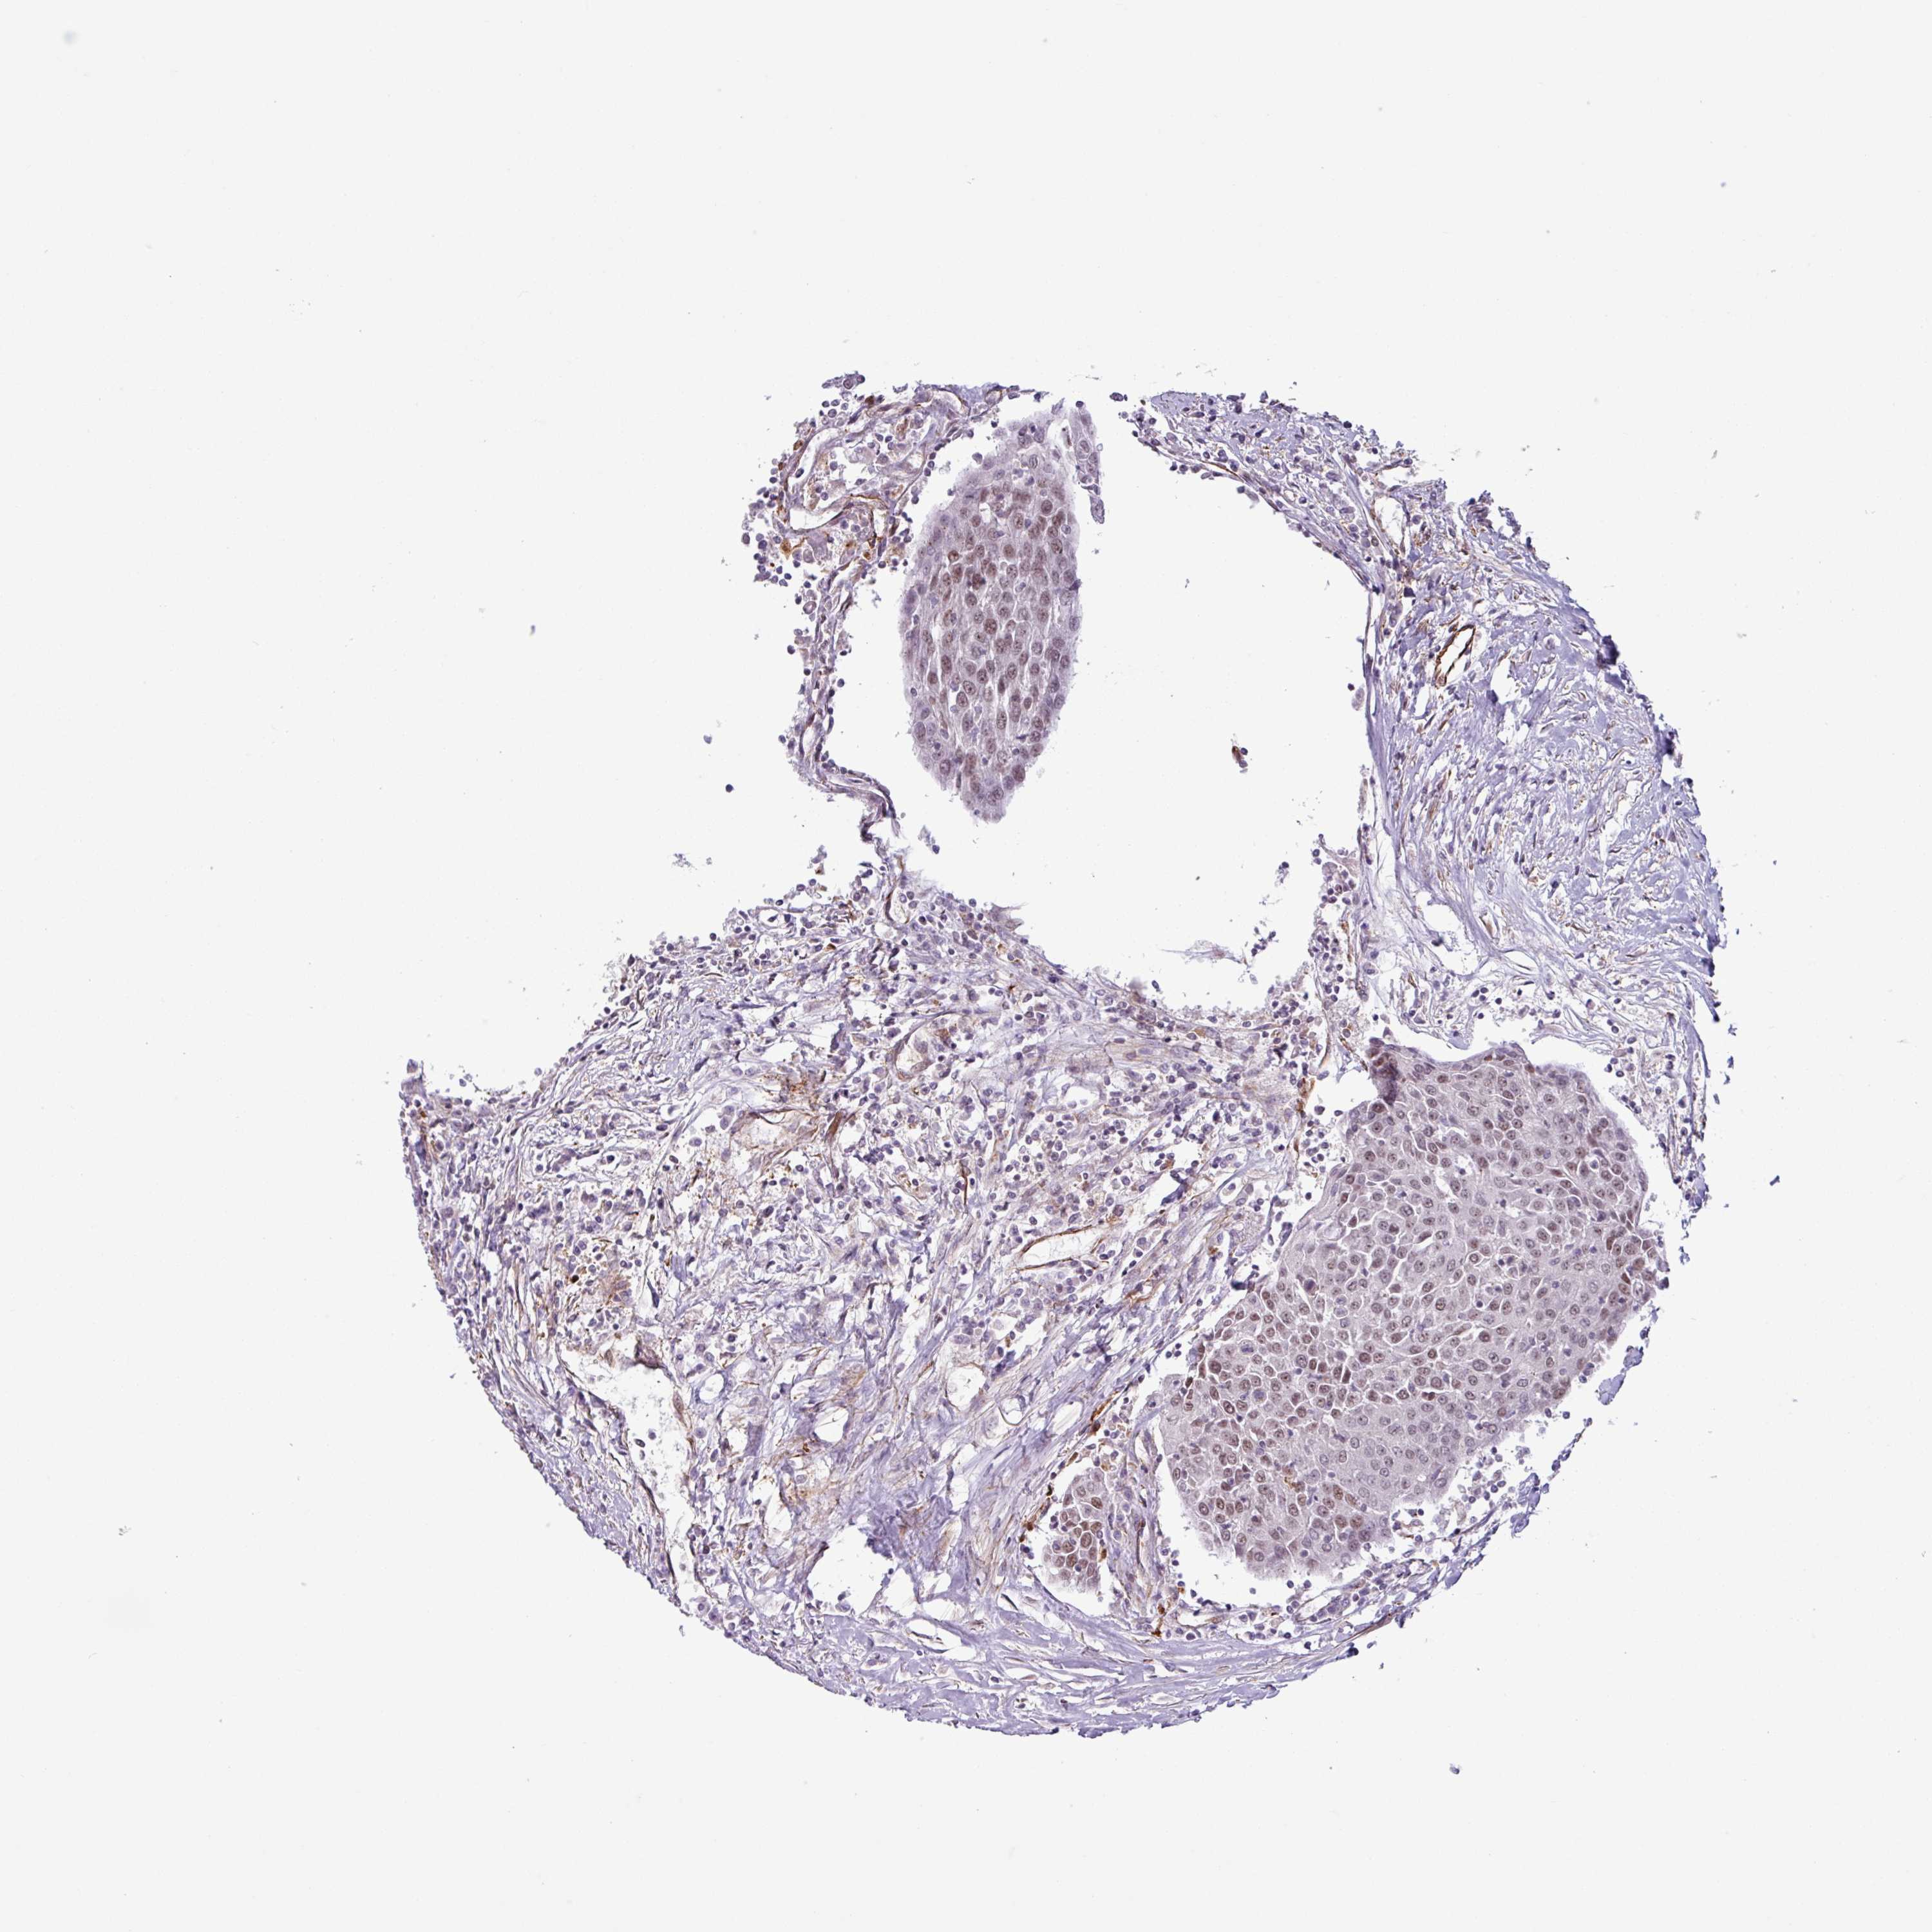

UROTHELIAL CANCER - Protein expressioni

A mouse-over function shows sample information and annotation data. Click on an image to view it in a full screen mode. Samples can be filtered based on level of antibody staining by selecting one or several of the following categories: high, medium, low and not detected. The assay and annotation is described here.

Note that samples used for immunohistochemistry by the Human Protein Atlas do not correspond to samples in the TCGA dataset.

Antibody stainingi

Antibody staining in the annotated cell types in the current human tissue is reported as not detected, low, medium, or high, based on conventional immunohistochemistry profiling in selected tissues. This score is based on the combination of the staining intensity and fraction of stained cells.

Each image is clickable and will lead to virtual microscopy that enables deeper exploration of all samples and also displays staining intensity scores, fraction scores and subcellular localization as well as patient and tissue information for each sample.

Antibody HPA043368

Staining

High

Medium

Low

Not detected

Intensity

Strong

Moderate

Weak

Negative

Quantity

>75%

75%-25%

<25%

None

Location

Nuclear

Cytoplasmic/membranous

Cytoplasmic/membranous,nuclear

Urothelial carcinoma, High grade

Urothelial carcinoma, NOS

Urothelial carcinoma, Low grade